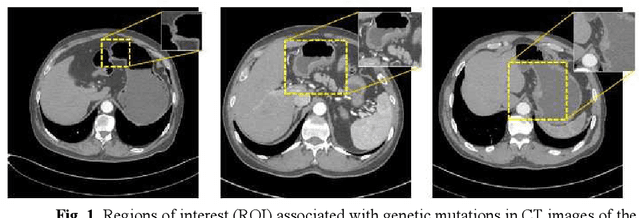

Abstract:Predicting the mutation status of genes in tumors is of great clinical significance. Recent studies have suggested that certain mutations may be noninvasively predicted by studying image features of the tumors from Computed Tomography (CT) data. Currently, this kind of image feature identification method mainly relies on manual processing to extract generalized image features alone or machine processing without considering the morphological differences of the tumor itself, which makes it difficult to achieve further breakthroughs. In this paper, we propose a pyramid focusing network (PFNet) for mutation prediction and classification based on CT images. Firstly, we use Space Pyramid Pooling to collect semantic cues in feature maps from multiple scales according to the observation that the shape and size of the tumors are varied.Secondly, we improve the loss function based on the consideration that the features required for proper mutation detection are often not obvious in cross-sections of tumor edges, which raises more attention to these hard examples in the network. Finally, we devise a training scheme based on data augmentation to enhance the generalization ability of networks. Extensively verified on clinical gastric CT datasets of 20 testing volumes with 63648 CT images, our method achieves the accuracy of 94.90% in predicting the HER-2 genes mutation status of at the CT image.